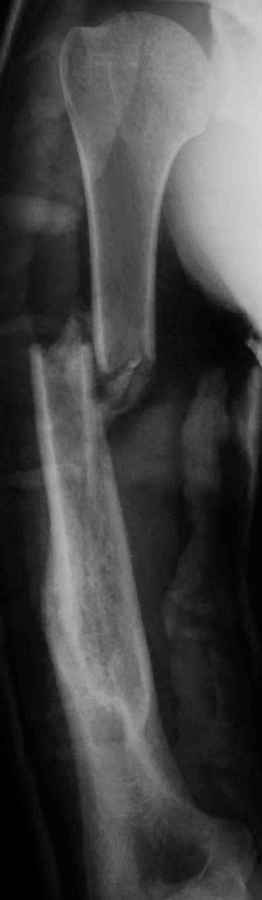

Результат консервативного лечения короткого косого перелома диафиза плеча врачами общей практики в условиях развивающейся страны у больного low social class

Предыдущий перелом плеча – пару лет назад ДТП. К сожалению, этот крайне важный жизненный опыт не изменил стиль вождения больногоПоследний перелом плеча – ДТП 2 мес назад. В связи с дефицитом как специалистов – ортопедов, так и операционного времени в принципе больной был осмотрен в приемном покое врачом общей практики, наложена U-образная гипсовая повязка и отправлен домой. Я впервые увидел больного через 6 нед после травмы, сделал снимки и снял повязку. Фотографии больного - 2 мес после травмы. снимки - при травме и через 6 недель

Вывод: Если плечо не трогать, оно нормально срастается.

Тот же самый вывод наукообразно: данное клиническое наблюдение свидетельствует, что консервативное лечение переломов диафиза плеча является патофизиологически оптимальным, приводит к удовлетворительному функциональному результату и явлеяется наиболее экономически щадящим как для больного, так и для системы государственного здравоохранения в целом.